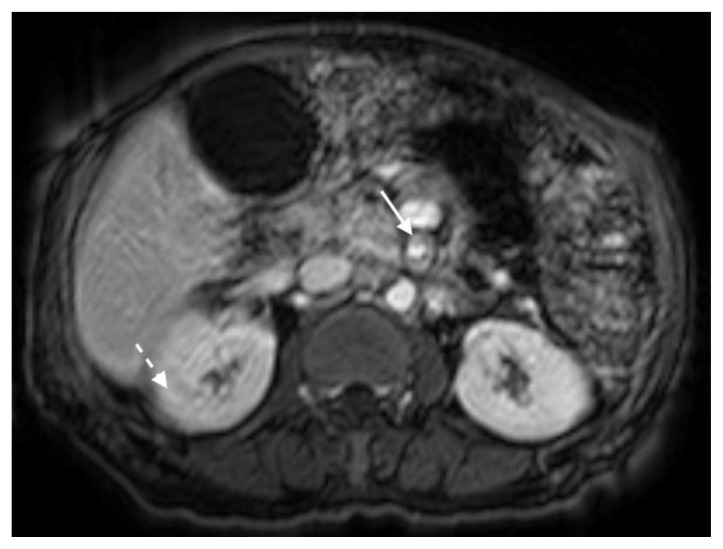

The MRI revealed soft tissue encased the proximal common bile duct (CBD) and biliary hilum, resulting in a 4cm-long stricture, with increased upstream intrahepatic biliary dilatation (Figures 5, 6). The hepatic parenchyma demonstrated diffuse heterogeneous enhancement, without a focal mass or pseudotumor, consistent with inflammatory changes. The pancreas demonstrated parenchymal T2 hyperintensity and T1 hypointensity with diffuse enhancement, including an enhancing peripheral soft tissue rind, again consistent with autoimmune pancreatitis (Figure 7). The kidneys also demonstrated multifocal regions of abnormal enhancement and restricted diffusion (Figure 9, 10). Persistent enhancing soft tissue surrounding the SMA and IMA was again noted (Figure 11, 12).

Figure 9.

78 year-old male with IgG4-related autoimmune disease.

Findings: Contrast enhanced MRI demonstrates enhancing soft tissue around the SMA (solid arrow). Also note lack of hypoenhancement in the renal kidneys (dashed arrow).

Technique: Axial T1-weighted fat saturation (6.7 mL Gadavist). 1.5T, TR = 5.86, TE = 0, 2.5 mm slice thickness.